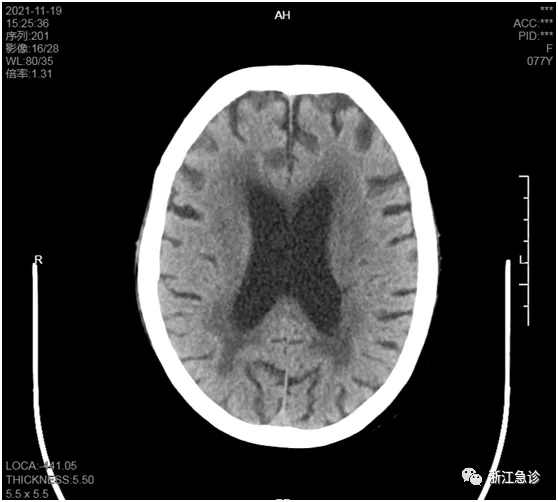

(入院前一天的頭顱CT)

另外,入院前一天頭顱CT是正常的,加上患者在吃強心藥,也容易誤導我們的思維。